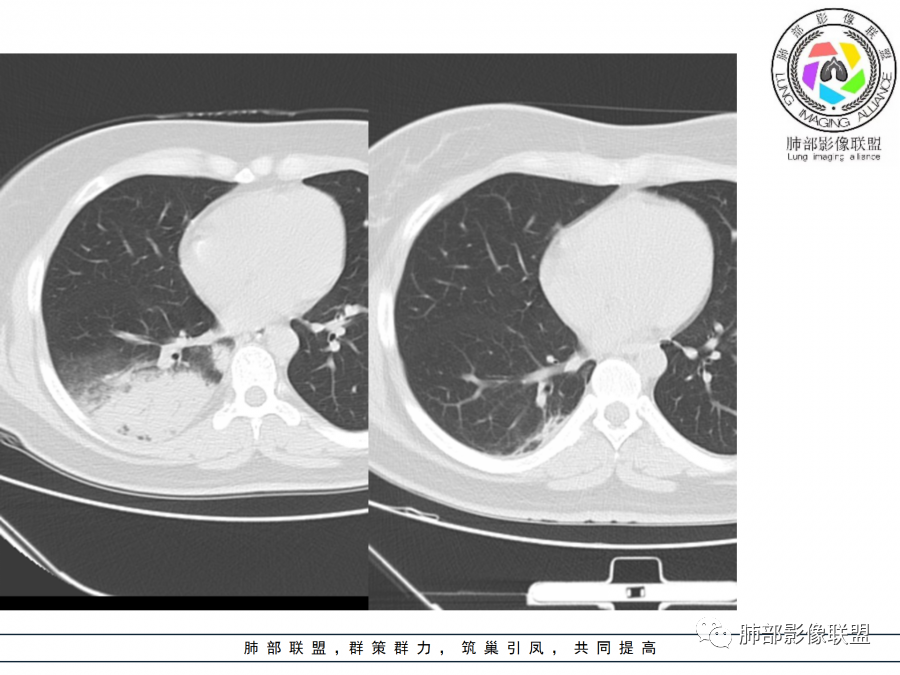

1)实变影为大小不等多中心性。

2)沿胸膜下分布趋势(不同于大叶性肺炎的肺叶“造型”)。

3)周围较大范围磨玻璃影及小叶间隔增厚。

4)病灶体积增大明显(叶间裂推移)。

3.腺病毒肺炎可以符合上述改变:实性密度,间质分布为主等。

4.隐球菌感染可以符合上述改变:胸膜下多中心实变密度为主,磨玻璃晕等。但隐球菌临床症状大多隐匿、迁延,影像变化缓慢。

5.本例患者血象高,影像渗出明显,尚不能排除混合感染可能。